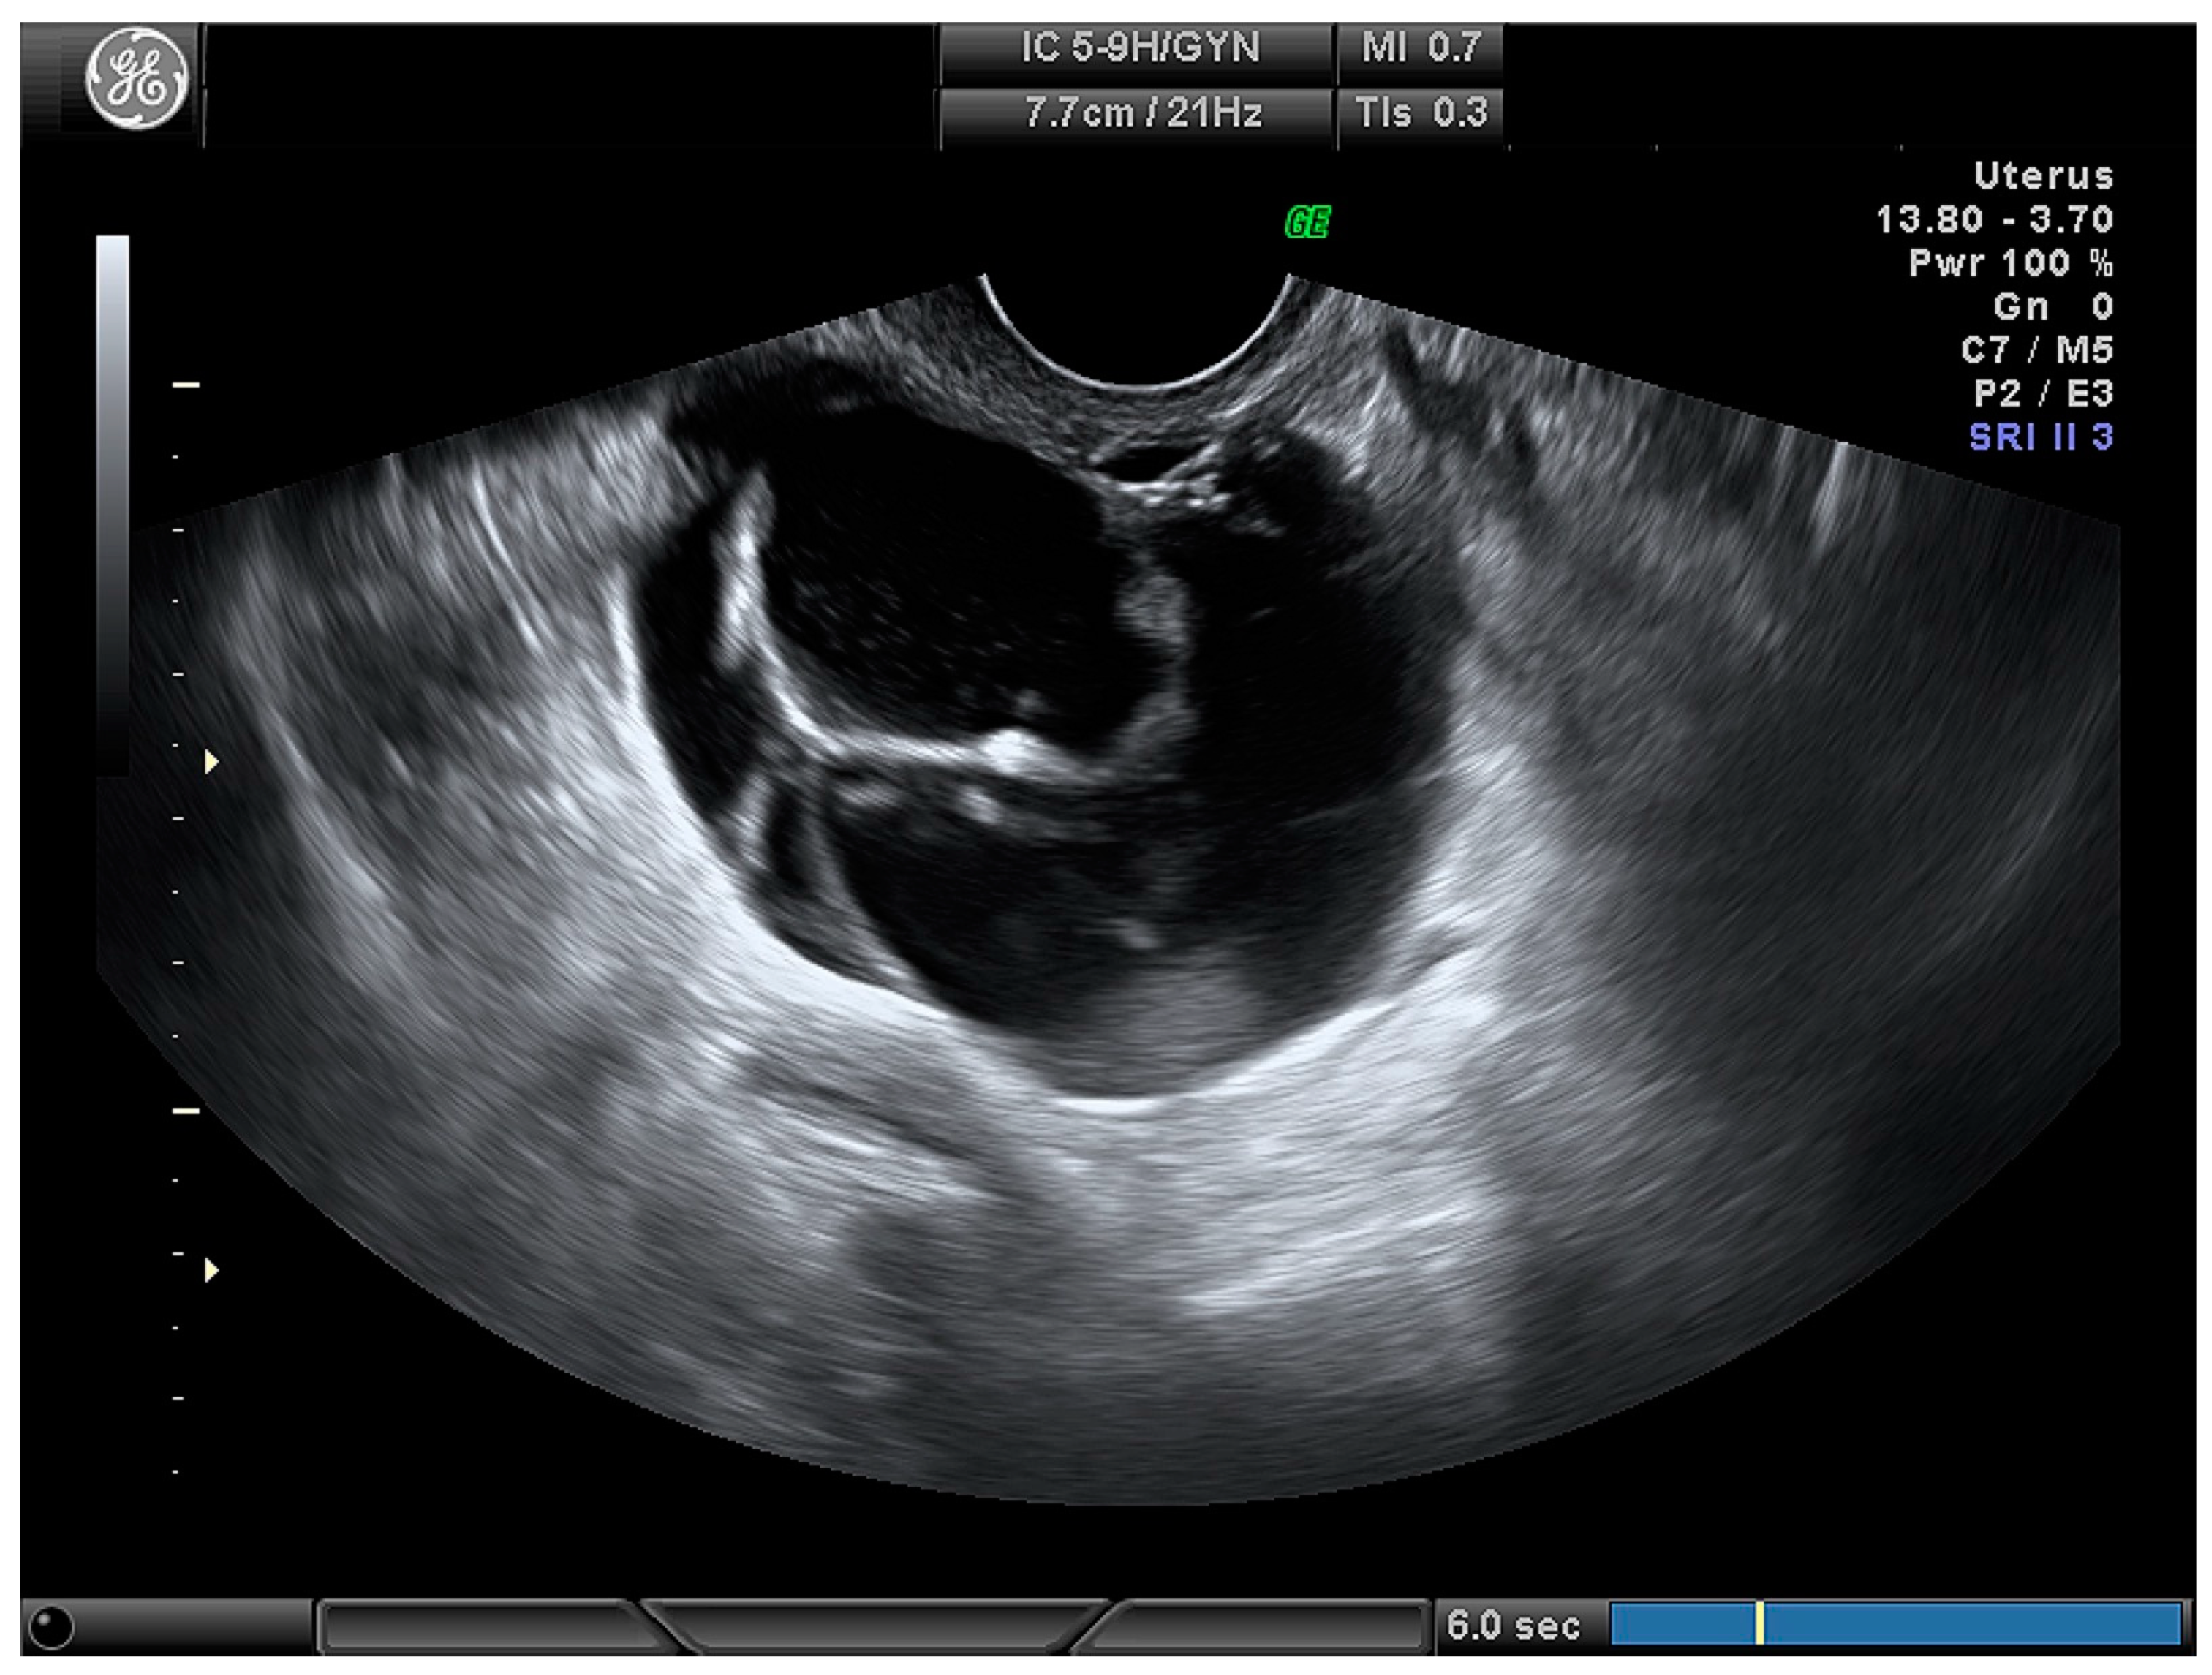

| Cystic (Figure 3) | 24 (28.2) |

| Cystic–solid (Figure 4) | 61 (71.8) |

| Number of papillary projections: | |

| More than 3 | 33 (38.8) |

| Cystic | 7 (12.3) | 12 (54.5) | |

| Cystic–solid | 50 (87.7) | 10 (45.5) | |

| Presence of papillary projections | 46 (80.7) | 8 (36.4) | p < 0.001 |